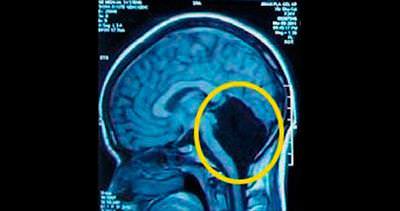

Çin'de başağrısı şikâyetiyle doktora giden 24 yaşındaki bir kadının beyninin bir kısmının olmadığı görüldü. Kadının beyninin olmadığı yerde ise beyin-omurilik sıvısıyla dolu olduğu belirtildi. Bilim insanları bu tür vakalar sayesinde beynin diğer yarısı olmadan eksik olan işlevleri nasıl telafi ettiğini araştırıyor. Kadın dünyada beyninin yarısı olmadığı tespit edilmiş 9 kişiden biri.